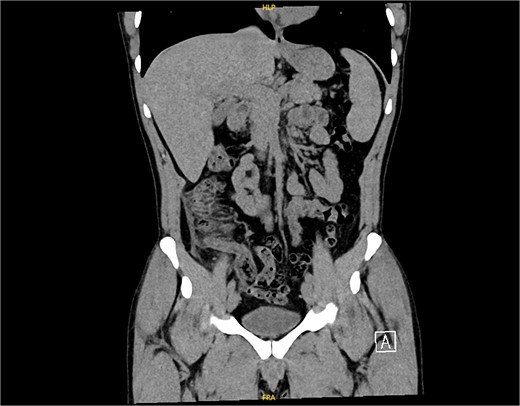

The non-contrast CT scan revealed a retrocecal appendix measuring 11 mm in diameter, with periappendiceal fluid and fat smudging, and reactive thickening of the cecum, indicating uncomplicated acute appendicitis. The patient was admitted to the surgical department and scheduled for a laparoscopic appendectomy (Figs 2 and 3).

CT scan picture with a coronal view showing acute inflamed appendix with peri-appendicular fat smudging, confirming the radiological finding of acute appendicitis.